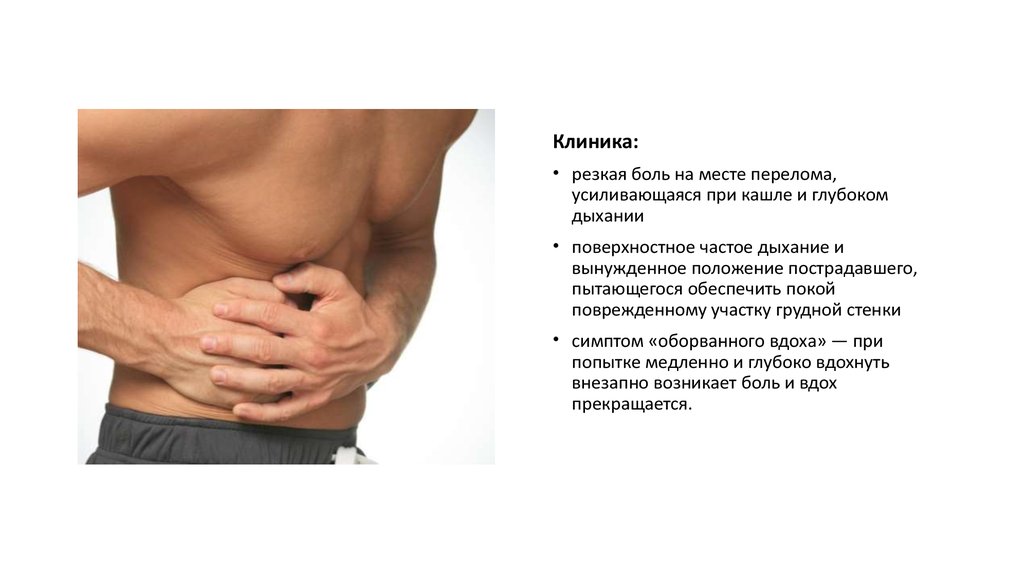

Причины и лечение боли в грудной клетке при кашле